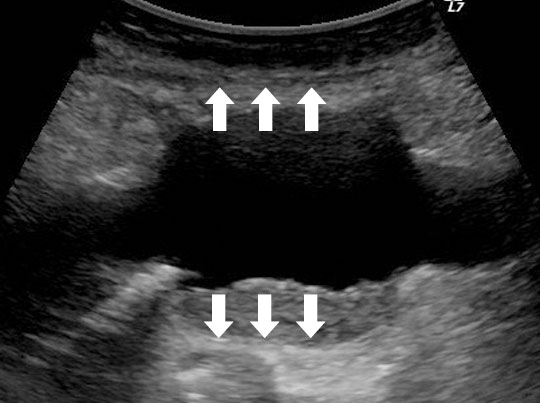

正常な腹部⼤動脈のエコー画像

正常な腹部⼤動脈は太さがほぼ⼀定

腹部⼤動脈瘤のエコー画像

部分的に拡張している部位が腹部⼤動脈瘤